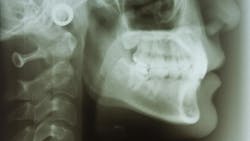

Osteoporosis

One of the many goals in dentistry is to preserve and maintain bone, as bone health plays a huge role in oral health. Approximately 10 million Americans have osteoporosis, and another 44 million have low bone density.10 Bone health is vital to healthy tooth structure and successful implant osseointegration. Panoramic radiographs are safe and excellent tools dental clinicians can use to screen patients for osteoporosis.

How and why to screen for osteoporosis